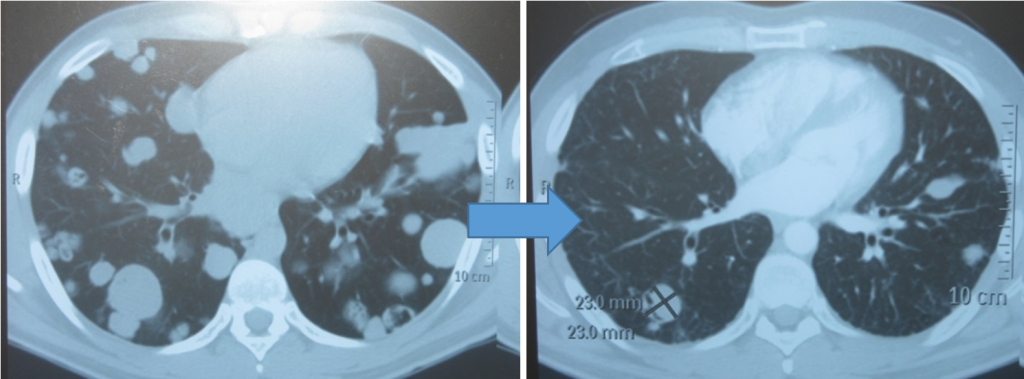

Показания к химиотерапии определяются степенью распространенности процесса, наличием легочных/внелегочных метастазов. Стандартным режимом химиотерапии при герминогенных опухолях является режим «BEP», включающий блеомицин, этопозид и цисплатин. Для пациентов с дыхательной недостаточностью, обширным поражением легких, во избежание легочной блеомициновой токсичности, как альтернативный вариант, может быть использованы режимы химиотерапии VIP (этопозид, ифосфамид, цисплатин) или ЕР (этопозид, цисплатин). Следует отметить, что при проведении системного лекарственного лечения необходимо строгое соблюдение временных рамок (начало очередного цикла проводится на 22 день). Для оценки эффективности химиотерапии каждые 2 цикла и после ее окончания проводится компьютерная томография исходных зон поражения, перед каждым циклом мониторинг уровня опухолевых маркеров. Рост маркеров на фоне лечения или после его завершения, а также замедление их снижения свидетельствует об активности опухолевого процесса и необходимости проведения второй линии химиотерапии. Перед проведением химиотерапии рекомендуется обдумать и решить вопрос о необходимости криоконсервации спермы.

Screenshot_2-1024x379.pngМетастазы в легких до лечения и после 4х циклов химиотерапии по схеме «ВЕР» (КТ грудной клетки)